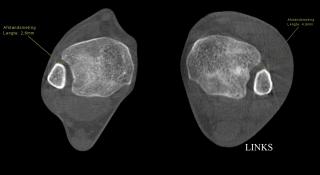

Letsel van de syndesmose, zichtbaar via PedCAT

Het beeld toont de verbreding van de ruimte tussen tibia en fibula links na enkelverstuiking met blijvende klachten suggestief voor laxiteit. Deze diastase is een indirect argument voor een letsel van de syndesmose, vaak een moeilijke klinische diagnose.